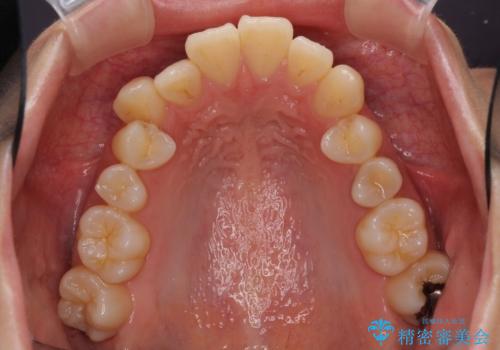

- 上の前歯、および下の歯列全体のでこぼこを気にして来院された患者様です。

インビザラインを用い、IPR(歯と歯の間を削る)と歯列全体を後方に移動させることで、歯並びを整えていくこととしました。

歯列全体を後方に移動させるため、下顎の親知らず2本を抜歯することとしました。